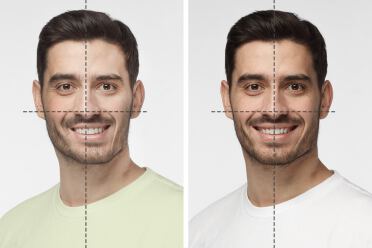

افرادی که نیاز به درمانهای ارتوسرجری دارند صرفاً مشکلات بهم ریختگی دندان و یا فاصله دندانی ندارند، در این افراد ناهنجاری هایی در روابط فک بالا و پایین وجود دارد که به چهره آنها لطمه وارد کرده ، لذا اولین اتفاق خوش آیند پس از پایان درمانهای جراحی ارتودنسی تغییر چهره افراد است که کاملا مشهود و نمایان است. افرادی که ارتود سرجری میکنند سطح بسیار بالایی از رضایت را در زندگی تجربه میکنند و 99% افراد از انجام ارتودنسی به عنوان بهترین اقدامی که در زندگی آنها تاثیرگذار بوده سخن میگویند. علاوه بر آن در کنار زیبایی که بدست می آورند، چون روابط فکین و نحوه جفت شدن دندانها بهبود چشمگیری پیدا میکند از غذا خورد و جویدن مناسب احساس رضایتمندی بیشتری دارند. در کل انجام این درمان برای افرادی با ناهنجاری فک توسط پزشک ارتودنسی شدیداً توصیه میشود.

غیر قرینگی صورت (Facial asymmetry)

در این موارد ناقرینگی صورت به دلیل رشد غیر قرینه ، ضربه یا تصادف و یا اختلالت ژنتیکی ایجاد میشود. ممکن است چانه یا قسمت میانی صورت و یا حتی گونه ها به یک سمت منحرف باشند . انحراف و غیر قرینگی در دندانها هم به تبعیت از استخوانها دیده میشود. درمان ارتودنسی و متعاقب آن جراحی جهت اصلاح این ناقرینگیها کمک شایانی به بهبود ظاهر بیمار، بهبود عمل جویدن و افزایش اعتماد به نفس وی مینماید.